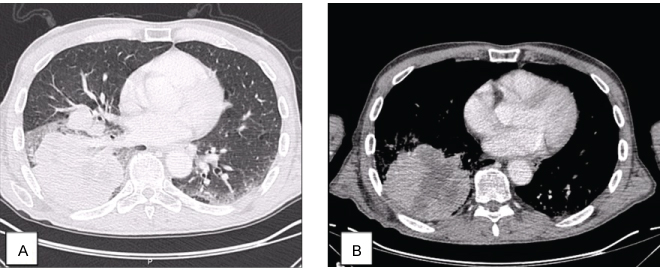

Chest radiography had an opacity on right hemithorax, on the lung base (Figure 1). The patient also performed a hands radiography that revealed no erosions (Figure 2). A full body computerized axial tomography (CT) scan was done to exclude neoplasia revealing "hypercaptant lymph node on supra-clavicular fossa 18 × 14 mm. Alveolar condensation without the bronchogram sign, rounded with hipocaptant regions suggestive of necrosis with pleural contact on right basal pyramid. Bronchi caliber reduction. Lymph node conglomerates and hipocaptant lymph nodes pre-vascular and para-tracheal on the right. These aspects are suggestive of primary lung lesion (Figure 3).

Figure 3: Chest CT: Alveolar condensation without the bronchogram sign, rounded with hipocaptant regions suggestive of necrosis, with pleural contact on right basal pyramid, lung window (A), and liver window (B). View Figure 3